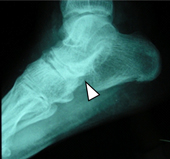

除了改善疼痛外,最重要的是希望能減少脊椎沾黏的併發症,如:嚴重的患者可能脊椎沾黏如竹竿,活動受限且無法正常地彎腰轉頭(如圖二),有些伴隨嚴重的周邊性下肢寡關節炎(如圖三)。

圖三、踝關節X光顯示關節腔狹窄,僵直性脊椎炎可能造成下肢膝蓋或腳踝的寡關節炎